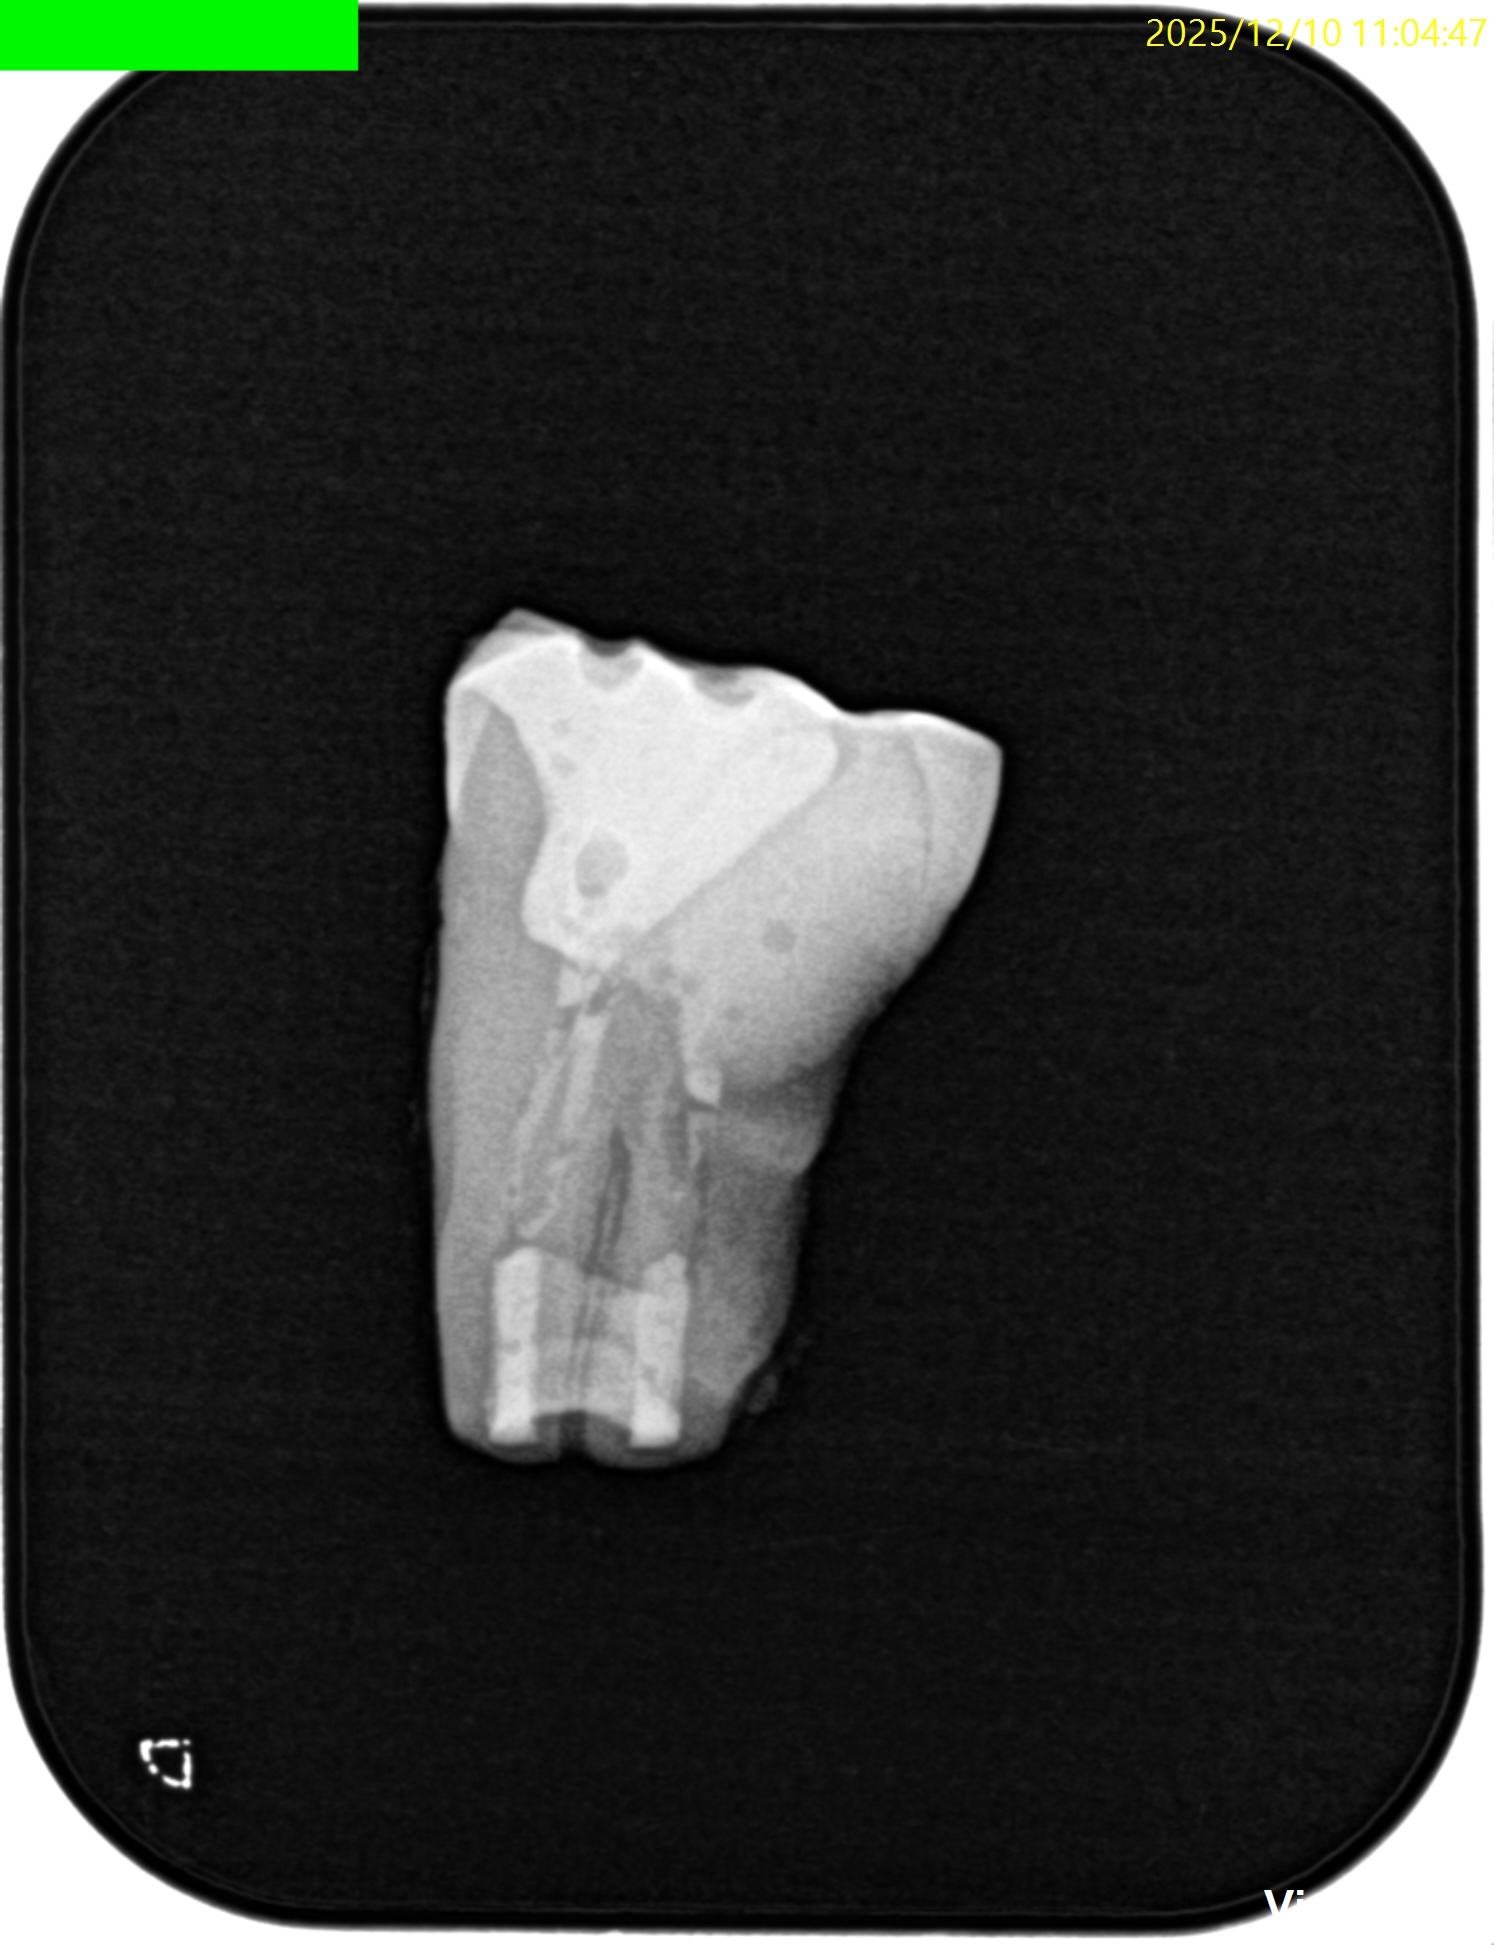

CBCT(2025.12.10)

ML

MB

D

遠心方向から見ると、

絶望的な状態であることがわかる。